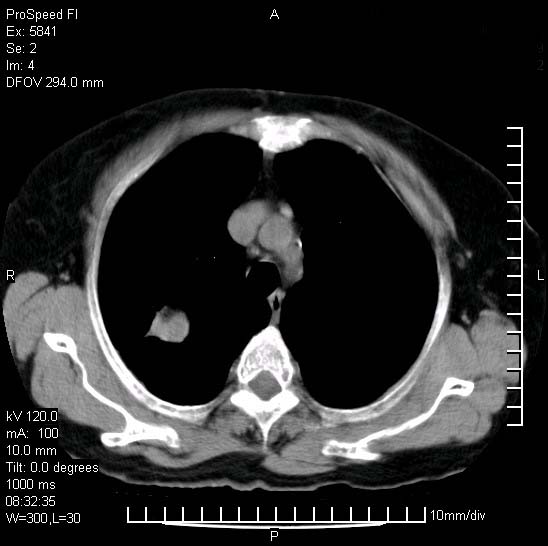

胸痛,咳嗽,气短一周,无发热。右上肺见一结节灶,边缘刺角,内见多个小钙化结节。考虑结核球?肿瘤? 余无异常没有上传。

考虑右肺上叶继发性肺结核,结核球形成。

慢性炎性病变,结核可能性大些。

为什么不考虑肺癌????????????